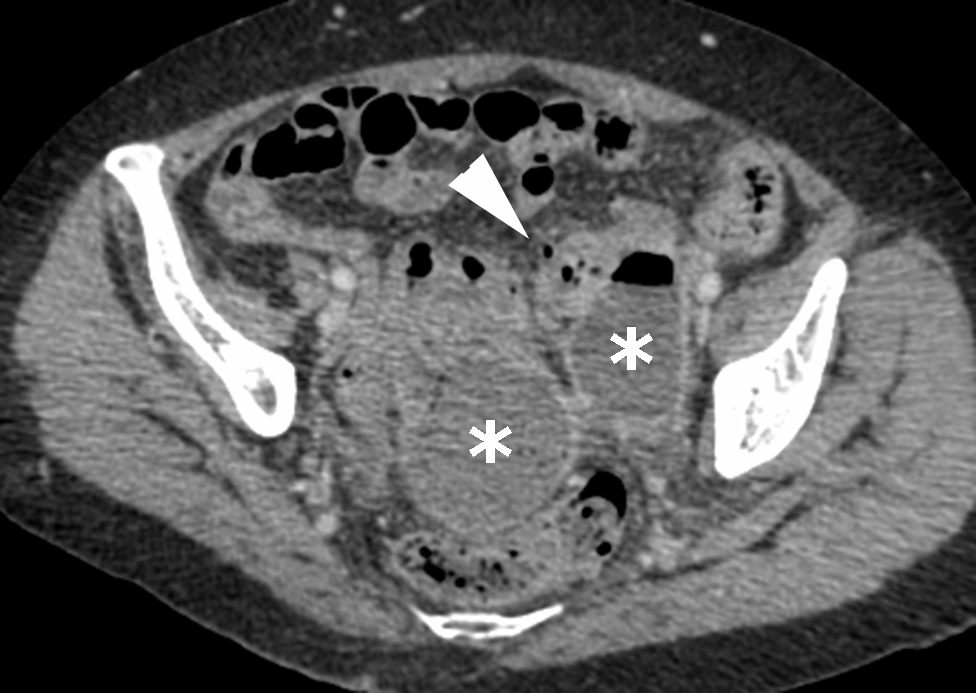

- L’abcès périsigmoïdien (figure 6.3) correspond à une collection de contenu liquidien ou hydroaérique, à parois rehaussées, à proximité du côlon diverticulaire.

Fig. 6.3 Diverticulite compliquée d’un abcès (Hinchey 2).

Scanner au temps portal après injection de produit de contraste iodé. Collection extradigestive pelvienne de contenu hydroaérique (∗) au contact d’un sigmoïde diverticulaire (tête de flèche), en rapport avec une diverticulite compliquée d’abcès périsigmoïdien.

Source : CERF, CNEBMN, 2022.